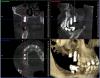

x3m Опубликовано 6 сентября, 2013 Автор Поделиться Опубликовано 6 сентября, 2013 (изменено) тест на витальность сейчас не проводился. мотивировать пациента не хочу - я рассказал свое видение ситуации.послушав авторитетные мнения, рассказал о вариантах на тему и прогнозах.дал ссылку на форум.написал письмо с вопросами автору установки имплантатов.созванивался и общался с этим же автором.как мне показалось, этого вполне достаточно, чтобы пациент самостоятельно принимал решение. теперь о вопросах.1. Где находится имплантат 16? Почему не видно кости?Визуально виден доступ в этой зоне: разрез от 14 до бугра по вершине а/о ...и торчащие заглушки. т.к. от доктора инфы я не получил, подозреваю открытый синус? меня смущает отсутствие кости у 16, реакция слизистой в гайморовой, положение платформы относительно 15 (с оглядкой на будущее протезирование), габариты будущей коронки на 16 (КТ в окклюзии). 2. наличие кортикалки вестибулярно у имплантата в позиции 15 - где она? 3. Четвертый сегмент. 45 и 46-й платформами находились над силизистой.В этот визит проводилось протезирование 4 сегмента.насколько я понял, протезирование (+44 консоль) - временное (пластмассовая облицовка), хотя... для чего оно здесь? вероятно, оно-таки постоянное (пациент не знает, доктор информацию не раскрыл)). Коронки - массивные нависающие края (2-3мм вглубь при зондировании микрорезьбы), формат коронок с отрицательным углом, под балконом - отложения налета, легко кровоточащая десна... еще смущает глубина погружения имплантатов вестибулярно - кмк, в кости лишь половина макрорезьбы... какой прогноз? фото пока выложить не могу, постараюсь на след.неделе. 4. второй сегмент.Что делаем с 27,28? Думается, удаление 27,28 и откр. синус.реакция в гайморовой - затёк из кармана? 5. 36. несколько смущает ось и погружение.хотя изо всего установленного это самый неплохой)) 6. Состояние во фронтальном участке после костной пластики.материал не там, где хотелось бы.остатки под носовым ходом (красным), объема ни вестибулярно, ни по высоте нет.автор предложил имплантацию в этой зоне не рассматривать.Линия улыбки, в принципе, невысокая, но не хочется, чтобы перегружали 11 и 23 мостом с розовой керамикой... Какова вероятность восстановления объема аутоблоками?(желтым указана небная кортикалка). Коллеги, буду благодарен за попунктовые ответы п.с. сорри за много букоФ и картинкоФ Изменено 6 сентября, 2013 пользователем x3m Ссылка на комментарий

Bier Опубликовано 6 сентября, 2013 Поделиться Опубликовано 6 сентября, 2013 открытый синус однозначно, на КТ видно окно, часть материала мигрировала в пазуху, пазуха вся в отеке. Ссылка на комментарий

kriokov Опубликовано 6 сентября, 2013 Поделиться Опубликовано 6 сентября, 2013 похоже по кт, что винт 15 вестибулярно закрутили, и кортикалки там и не будет. Синус почти тотально со снижением пневматизации, чего там полипоз или полипоз и жидкость х\з. По поводу 16- похоже на открытый синус, но графт как то не плотно, и винт похоже только 2 мм за нативную кость цепляется. имхо. Странно, что оператор обьясниться не хочет, у всех косяки бывают, Ссылка на комментарий

Bier Опубликовано 12 сентября, 2013 Поделиться Опубликовано 12 сентября, 2013 1. имплантат 16з стоит своей частью в полости пазухи, выполнен синуслифтинг. Вокруг имплантата виден остеотропный материал слабо рентген контрастный. Своей коронарной частью имплантат стоит в мягких тканях на 4 мм, что делает прогноз на его дальнейшую жизнь сомнительным. 2. имплантат 15 з расположен слишком вестибулярно, кортикальная пластинка либо очень тонкая либо ее нет. Прогноз неблагоприятный.3. Необходимо как минимум перепротезирование. Прогноз оценивать исходя из наличия или отсутствия гноетечения и стабильности имплантатов. Возможно можно ограничиться увеличением ЗКПД и адекватным протезированием. При наличии гнойного перимплантита рекомендовано удаление. Прогноз сомнительный.4.Согласен, удаляем. Реакция в гайморовой может быть и от кармана, а может быть остаточными являениями. Не критичны для синуслифтинга.5.36I я бы сохранил.6.объем кости для имплантации неадекватный. Для восстановления аутоблоки прогноз сомнительный. Я выступаю либо за грамотновыполненный GBR либо за 3D по Кюри. 2 Ссылка на комментарий